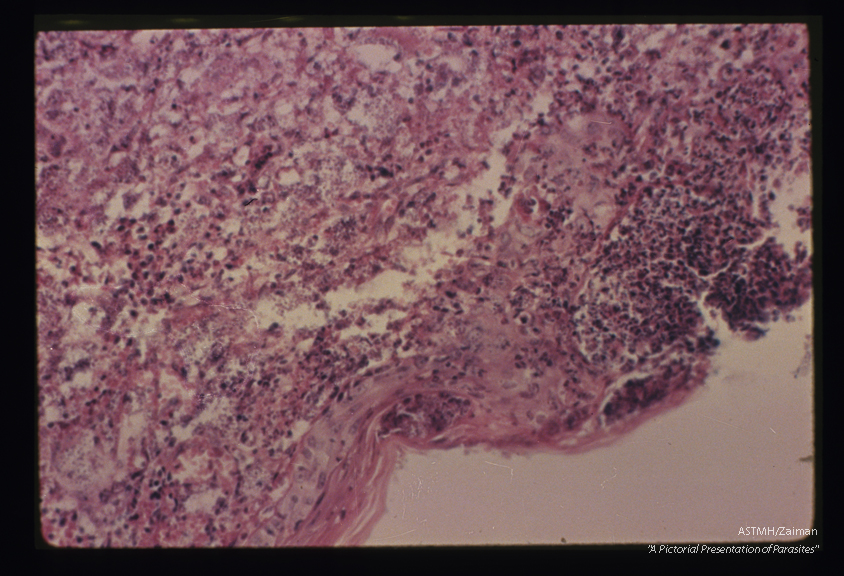

Low power view of section of ulcer. The epidermis is absent over the open ulcer. Adjacent epidermis is markedly thinned. There is destruction and inflammation below the epithelium.

Leishmania tropica

Description: Low power view of section of ulcer. The epidermis is absent over the open ulcer. Adjacent epidermis is markedly thinned. There is destruction and inflammation below the epithelium.